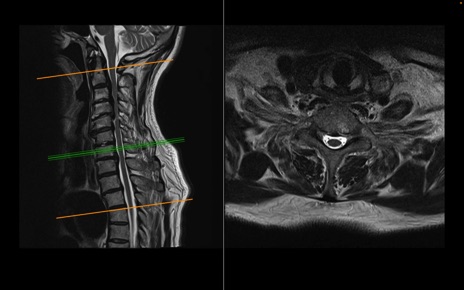

頚椎MRI

T2WI(横断像)

T2WI(矢状断像)